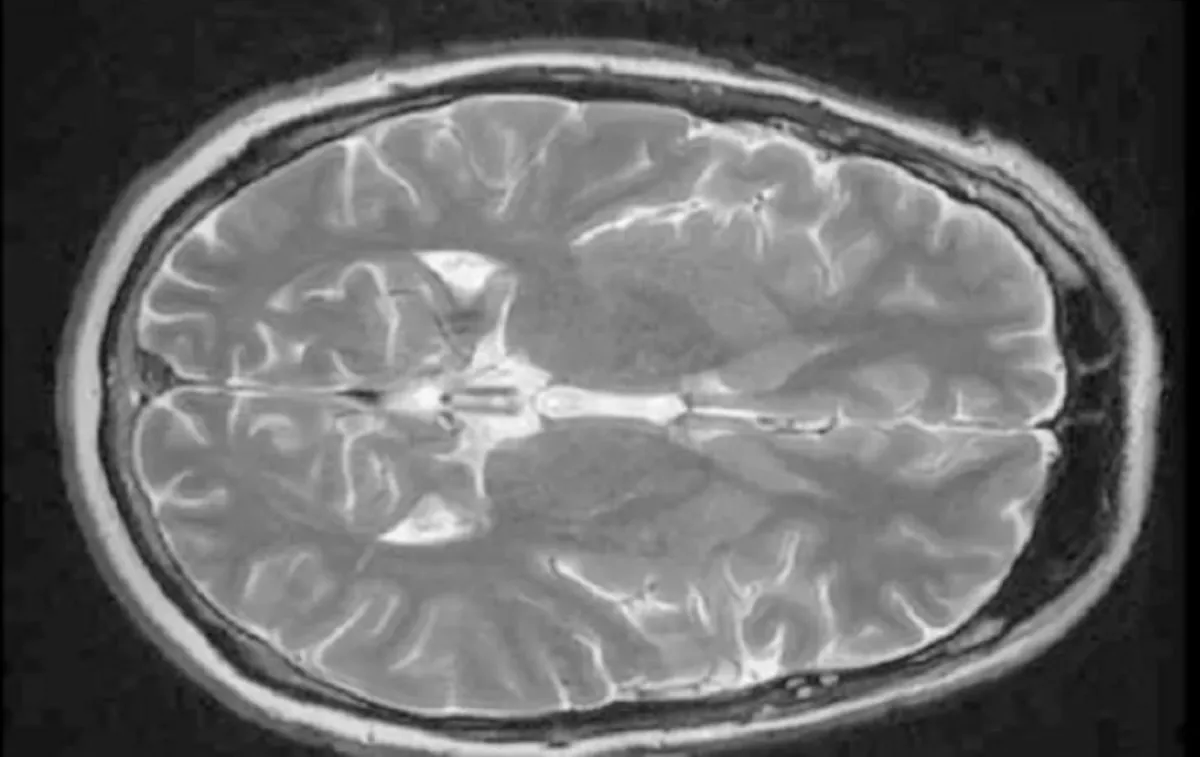

بحث جديد نشر هذا الأسبوع، يقول إن جزءًا جانبيًا في الجهة اليمنى من القشرة الجبهية (rVLPFC) يعتبر مسؤولاً عن إدخال المعلومات ذات العلاقة في سياق الأمر الذي تنوي القيام به، ومن ثم تحدث الخطة الأساسية التي كنت تنوي القيام بها.